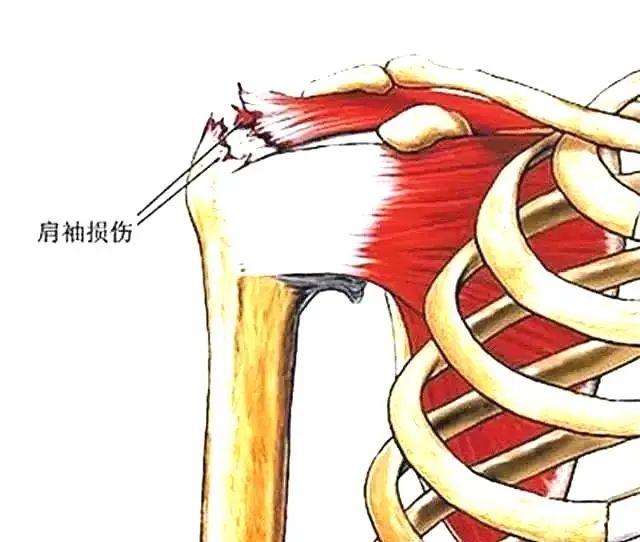

肩袖损伤

由于慢性积累性劳损或者一次急性损伤导致肩部疼痛,伴有主动活动时明显疼痛。主动活动受限明显,但被动活动影响不明显。需要肌骨超声或者肩部MR 确诊。